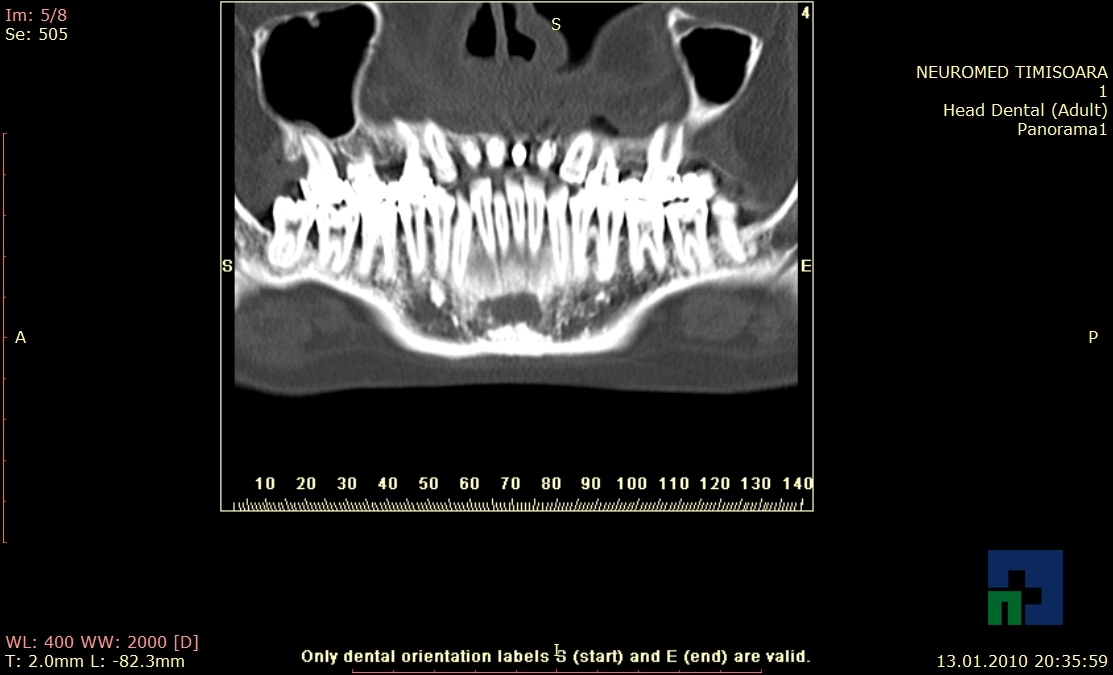

- Diagnosticul fracturilor:

- Unice

- Multiple

- Cu înfundare